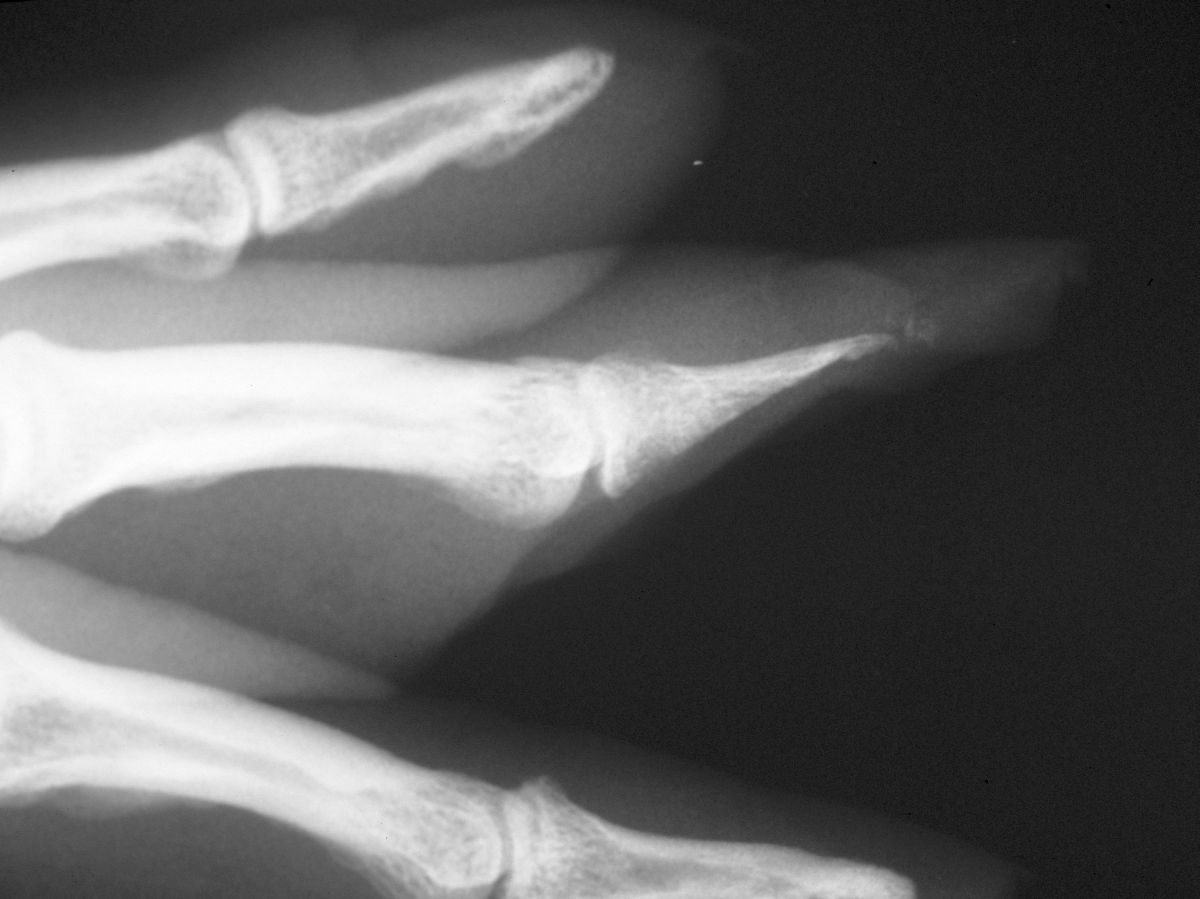

| Case

4. A dog bit off this young man's index fingertip. Although the PA Xray looks as though the bone was kept, additional views show an amputation through the tuft. |

| The defect. |